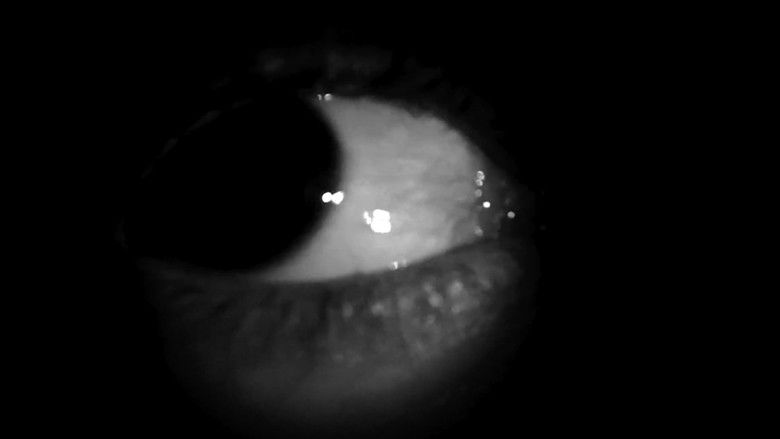

Кадры